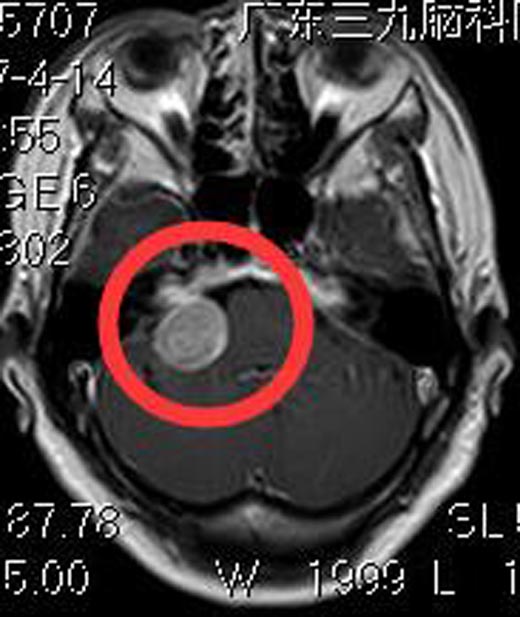

入住广东三九脑科医院综合神经外科,进一步头颅MR检查,显示:右侧桥小脑角占位性病变,大小约2.6cm×2.0cm×2.5cm,考虑听神经瘤。

由鲁明主任主刀,在全麻下行右侧桥小脑角占位切除术,术中显微镜下见肿瘤位于右侧桥小脑角,质软,珍珠样,血供少,予分块切除,面、听神经保留完整,肿瘤全切。术后叶奶奶没有面瘫、吞咽困难、饮水呛咳等后组颅神经损害症状。术后病理回报:神经鞘瘤。

▲手术前